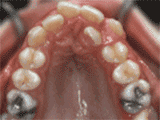

Crowded dentition, lack of anterior teeth occlusion, asymmetrical midline of upper and lower teeth, narrow dental arch, and ectopic eruption of the upper canines. After professional assessment without any tooth extractions, the result of orthodontic treatment is as follows: